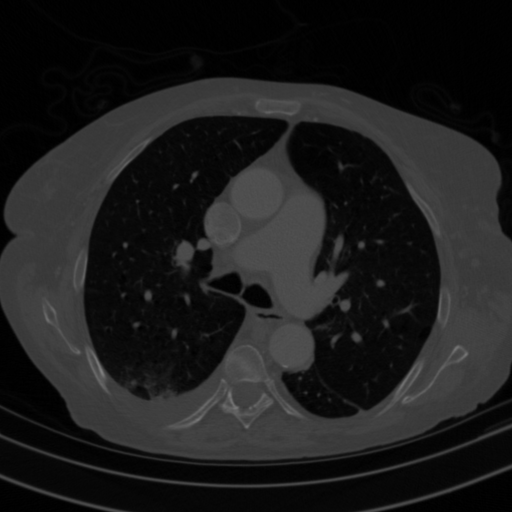

Original VENOUS CT scan

Full window (WL 1023.5, WW 4095 β†’ Low βˆ’1024, High +3071)

Lung window (WL -600, WW 1500 β†’ Low βˆ’1350, High +150)